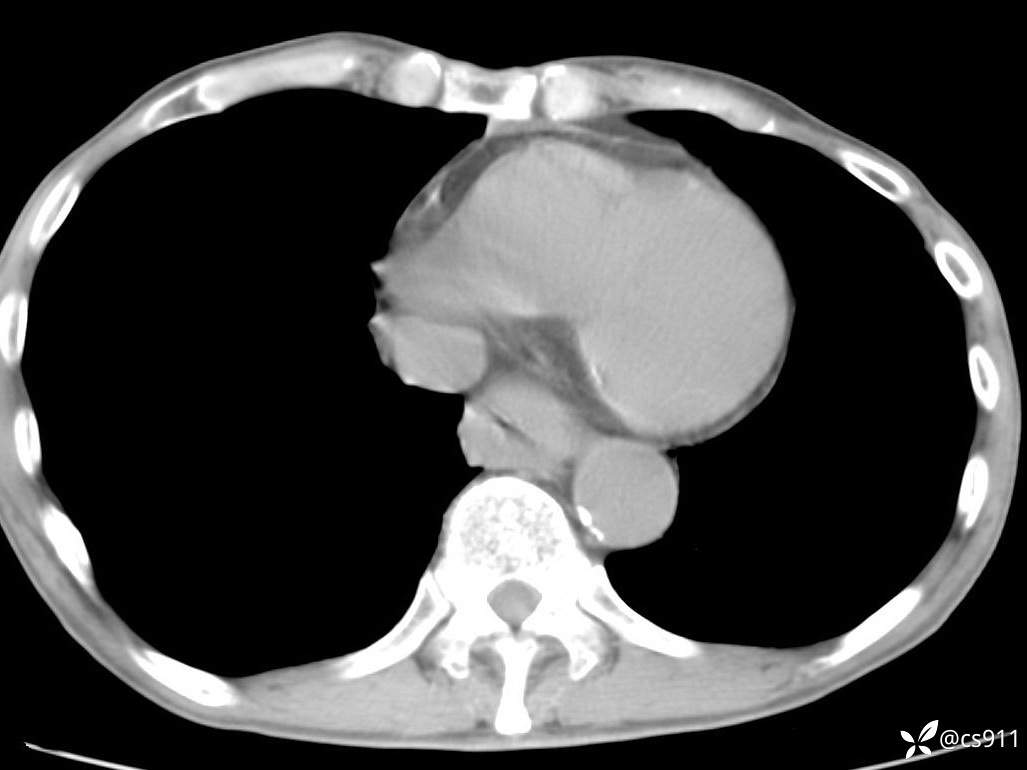

急腹症之急诊CT,原因?答案公布

男,77岁,腹痛、腹胀伴恶心呕吐1天。呕吐胃内容物,非喷射性呕吐,有咖啡色样胃内容物,诉有胃穿孔病史。查体:全腹平,下腹部压痛,全腹无反跳痛,叩诊呈浊音,移动性浊音阴性,肠鸣音减弱,1-2次/分。肛检:直肠未扪及明显肿物,可触及大量粪块。

血淀粉酶(AMY) HH 1859 U/L 35-135

癌胚抗原(CEA) H 27.44 ng/ml 0-5